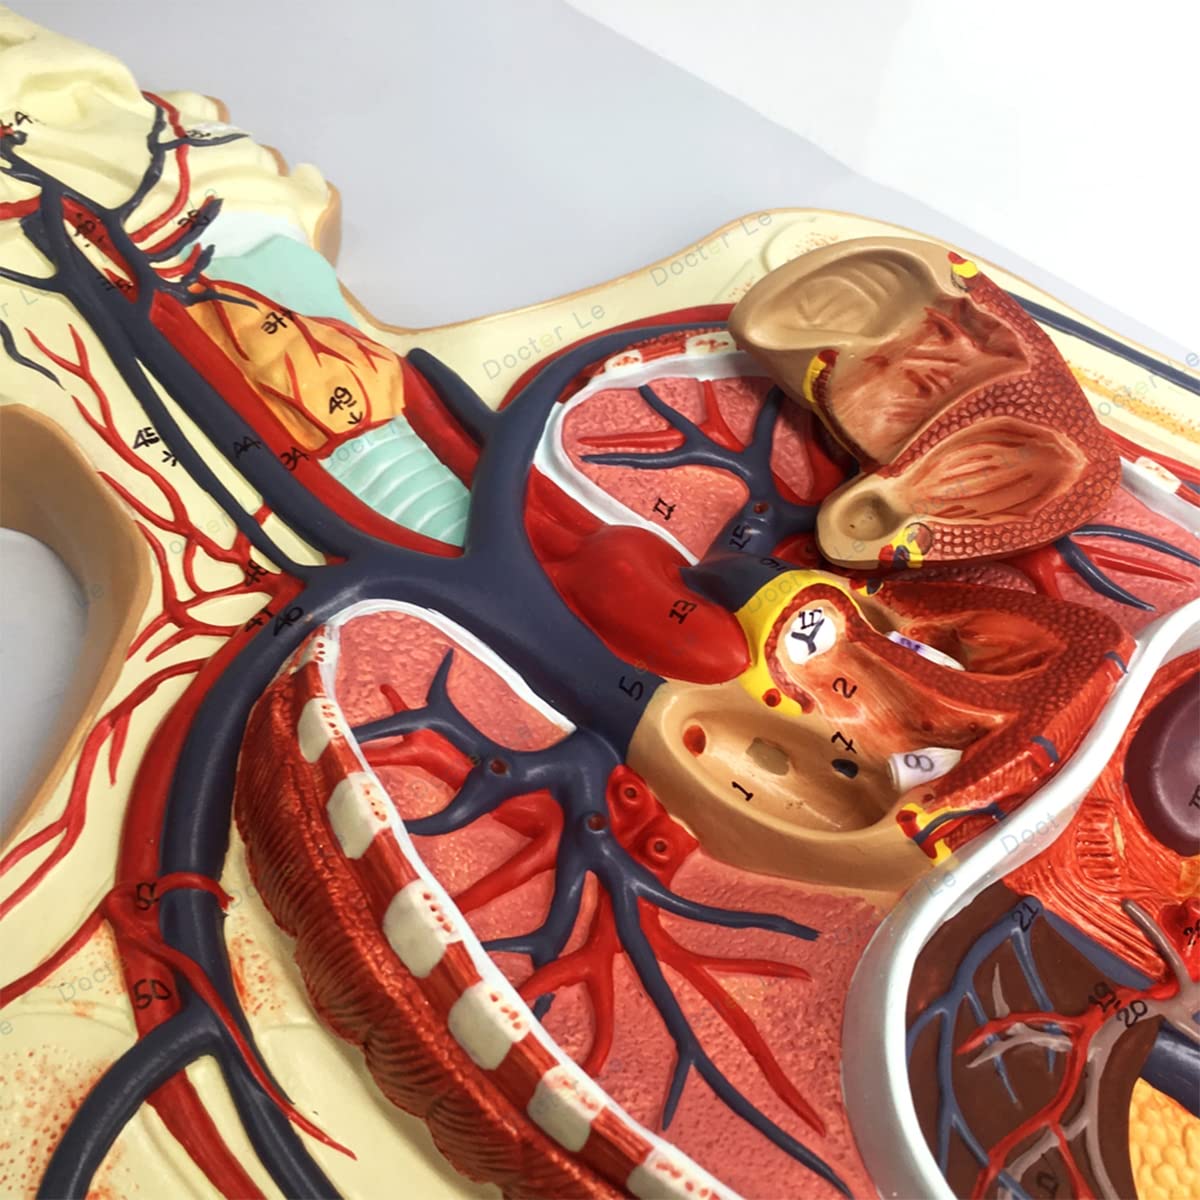

- Features: This model shows the structure of blood circulation in various parts of the human body. The circulatory system is the channel through which blood flows in the body and is divided into two parts: the cardiovascular system and the lymphatic system. Blood circulation route: superior and inferior vena cava → right atrium → right ventricle → pulmonary artery - → alveolar surrounding → pulmonary veins - >> left atrium → left ventricle → aorta - → systemic tissues (except lung). Product Size: Using this model helps to understand the composition and structure of human blood circulation. The size of the model is 1/2 the size of the human blood circulatory system. Product size: 90*30 cm/35.4*11.8 inches. High Quality: High-quality prototypes, sturdy hand-made, not fragile, made of high-quality environmentally friendly PVC, fine workmanship, creating good objects with clear shapes and rich details. Meticulous workmanship: The model has meticulous workmanship, realistic details, clear texture, easy to use and easy to observe. This product comes with a base, which is convenient for learning and teaching. Good Teaching Aids: This collection is designed for anatomy professionals and students. We are sure you will love these models. Can also be given as a gift to educators or doctors, excellent educational tool for students/teachers/professionals.

Product Specifications:Product name: Human Blood Circulatory System Model Product Type: Medical Teaching Model Product material: PVCProduct use: medicine, school, hospital, medical giftPackage list:Human Blood Circulatory System Model *1Notice:The monitor calibration is different, and the color of the object shown in the photo may be slightly different from the actual product. Please refer to the actual product.